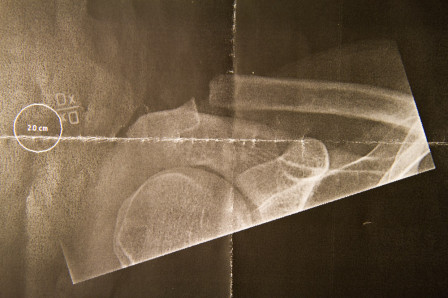

Slutligen: Hur var det att cykla på nästa års hojar? Ingen aning, jag var så överladdad att jag drog ut för ett stup och kraschade axeln på det femte åket. Subluxation sa doktorn. Ge mig piller sa jag.